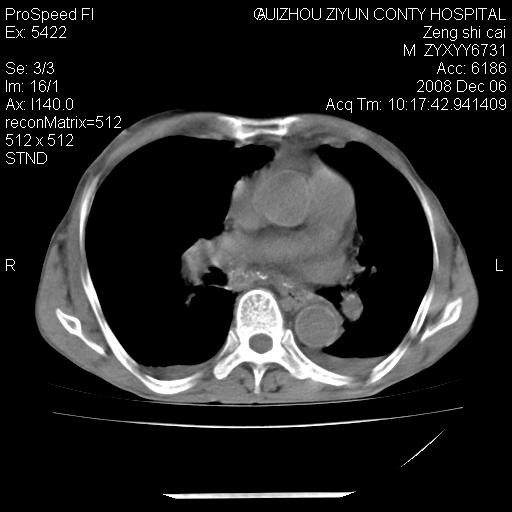

标题: CT16961:M、71岁,咳嗽半年,无血痰;胸片示右肺占位。 [打印本页]

标题: CT16961:M、71岁,咳嗽半年,无血痰;胸片示右肺占位。

右肺癌并纵隔淋巴结及胸膜转移可能性大

右肺癌并纵隔淋巴结及胸膜转移。建议气管镜

右肺纵隔型肺癌伴纵隔淋巴结及胸膜转移!

右肺纵隔型肺癌伴纵隔淋巴结转移!双侧胸水!

1)考虑右肺上叶纵隔型肺癌伴纵隔淋巴结转移。2)心包积液,双侧胸腔积液。

右肺癌并纵隔淋巴转移,腹膜后转移可能性大,两侧胸腔积液

右肺上叶纵隔型肺癌伴纵隔淋巴结转移。心包积液,双侧胸腔积液。

右上肺癌并纵隔淋巴结及胸膜转移。

建议强化!主要鉴别是淋巴瘤与肺癌淋巴结转移。

右肺纵隔型肺癌伴纵隔淋巴结及胸膜转移